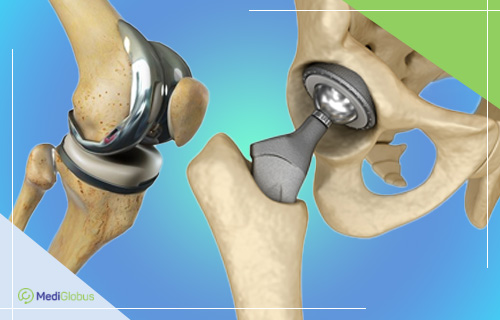

Примеры протезов коленных суставов Zimmer

Раздел: Образы вокруг